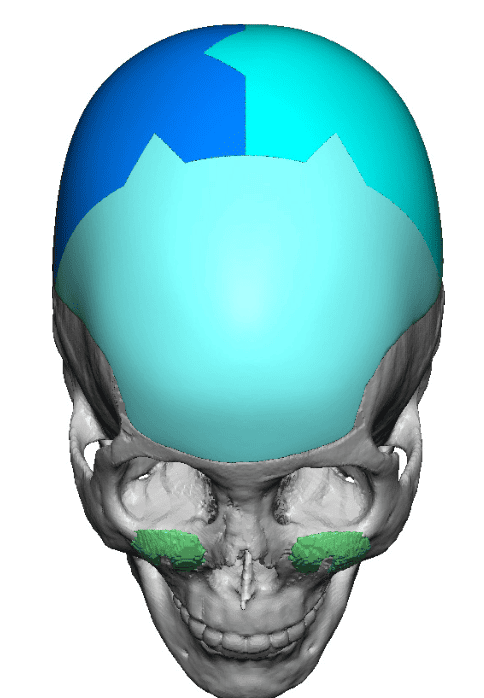

Patient 84

Desire for change of head shape from front view form an inverted V shape to a rounder and wider head shape.

Placement of custom extended forehead-temporal implants through incisions in the crease behind the ear. (he had a prior back of head skull implant which is green in the implant designs and which the head widening implants partially covered it)

Desire for change of head shape from front view form an inverted V shape to a rounder and wider head shape.

Placement of custom extended forehead-temporal implants through incisions in the crease behind the ear. (he had a prior back of head skull implant which is green in the implant designs and which the head widening implants partially covered it)